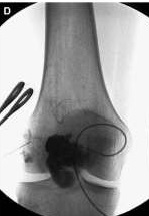

Venous Efflux Patterns This figure represents different phlebography pattern of venous malformation